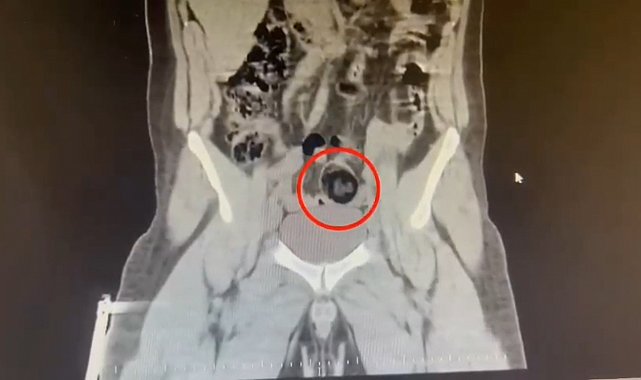

Kars Emniyet Müdürlüğü Narkotik Suçlarla Mücadele Şube Müdürlüğünce, savcılık koordinesinde kent merkezinde uluslararası uyuşturucu madde ticareti yapan kurye şahıslara yönelik operasyon düzenlendi. Bu kapsamda narkotik ekiplerince durdurulan yolcu otobüsünde İranlı kurye yakalanarak gözaltına alındı. Şüpheli hareketler sergilen kurye götürüldüğü hastanede yapılan iç beden muayenesinde makatında cisim olduğu anlaşıldı. Kuryenin makatındaki 105,98 gram metamfetamin gerçekleştirilen cerrahi müdahaleyle çıkarıldı. Gözaltına alınarak emniyete getirilen kurye, çıkarıldığı mahkemece "TCK-188 uyuşturucu veya uyarıcı madde imal ve ticareti yapmak" suçundan tutuklanarak cezaevine gönderildi.